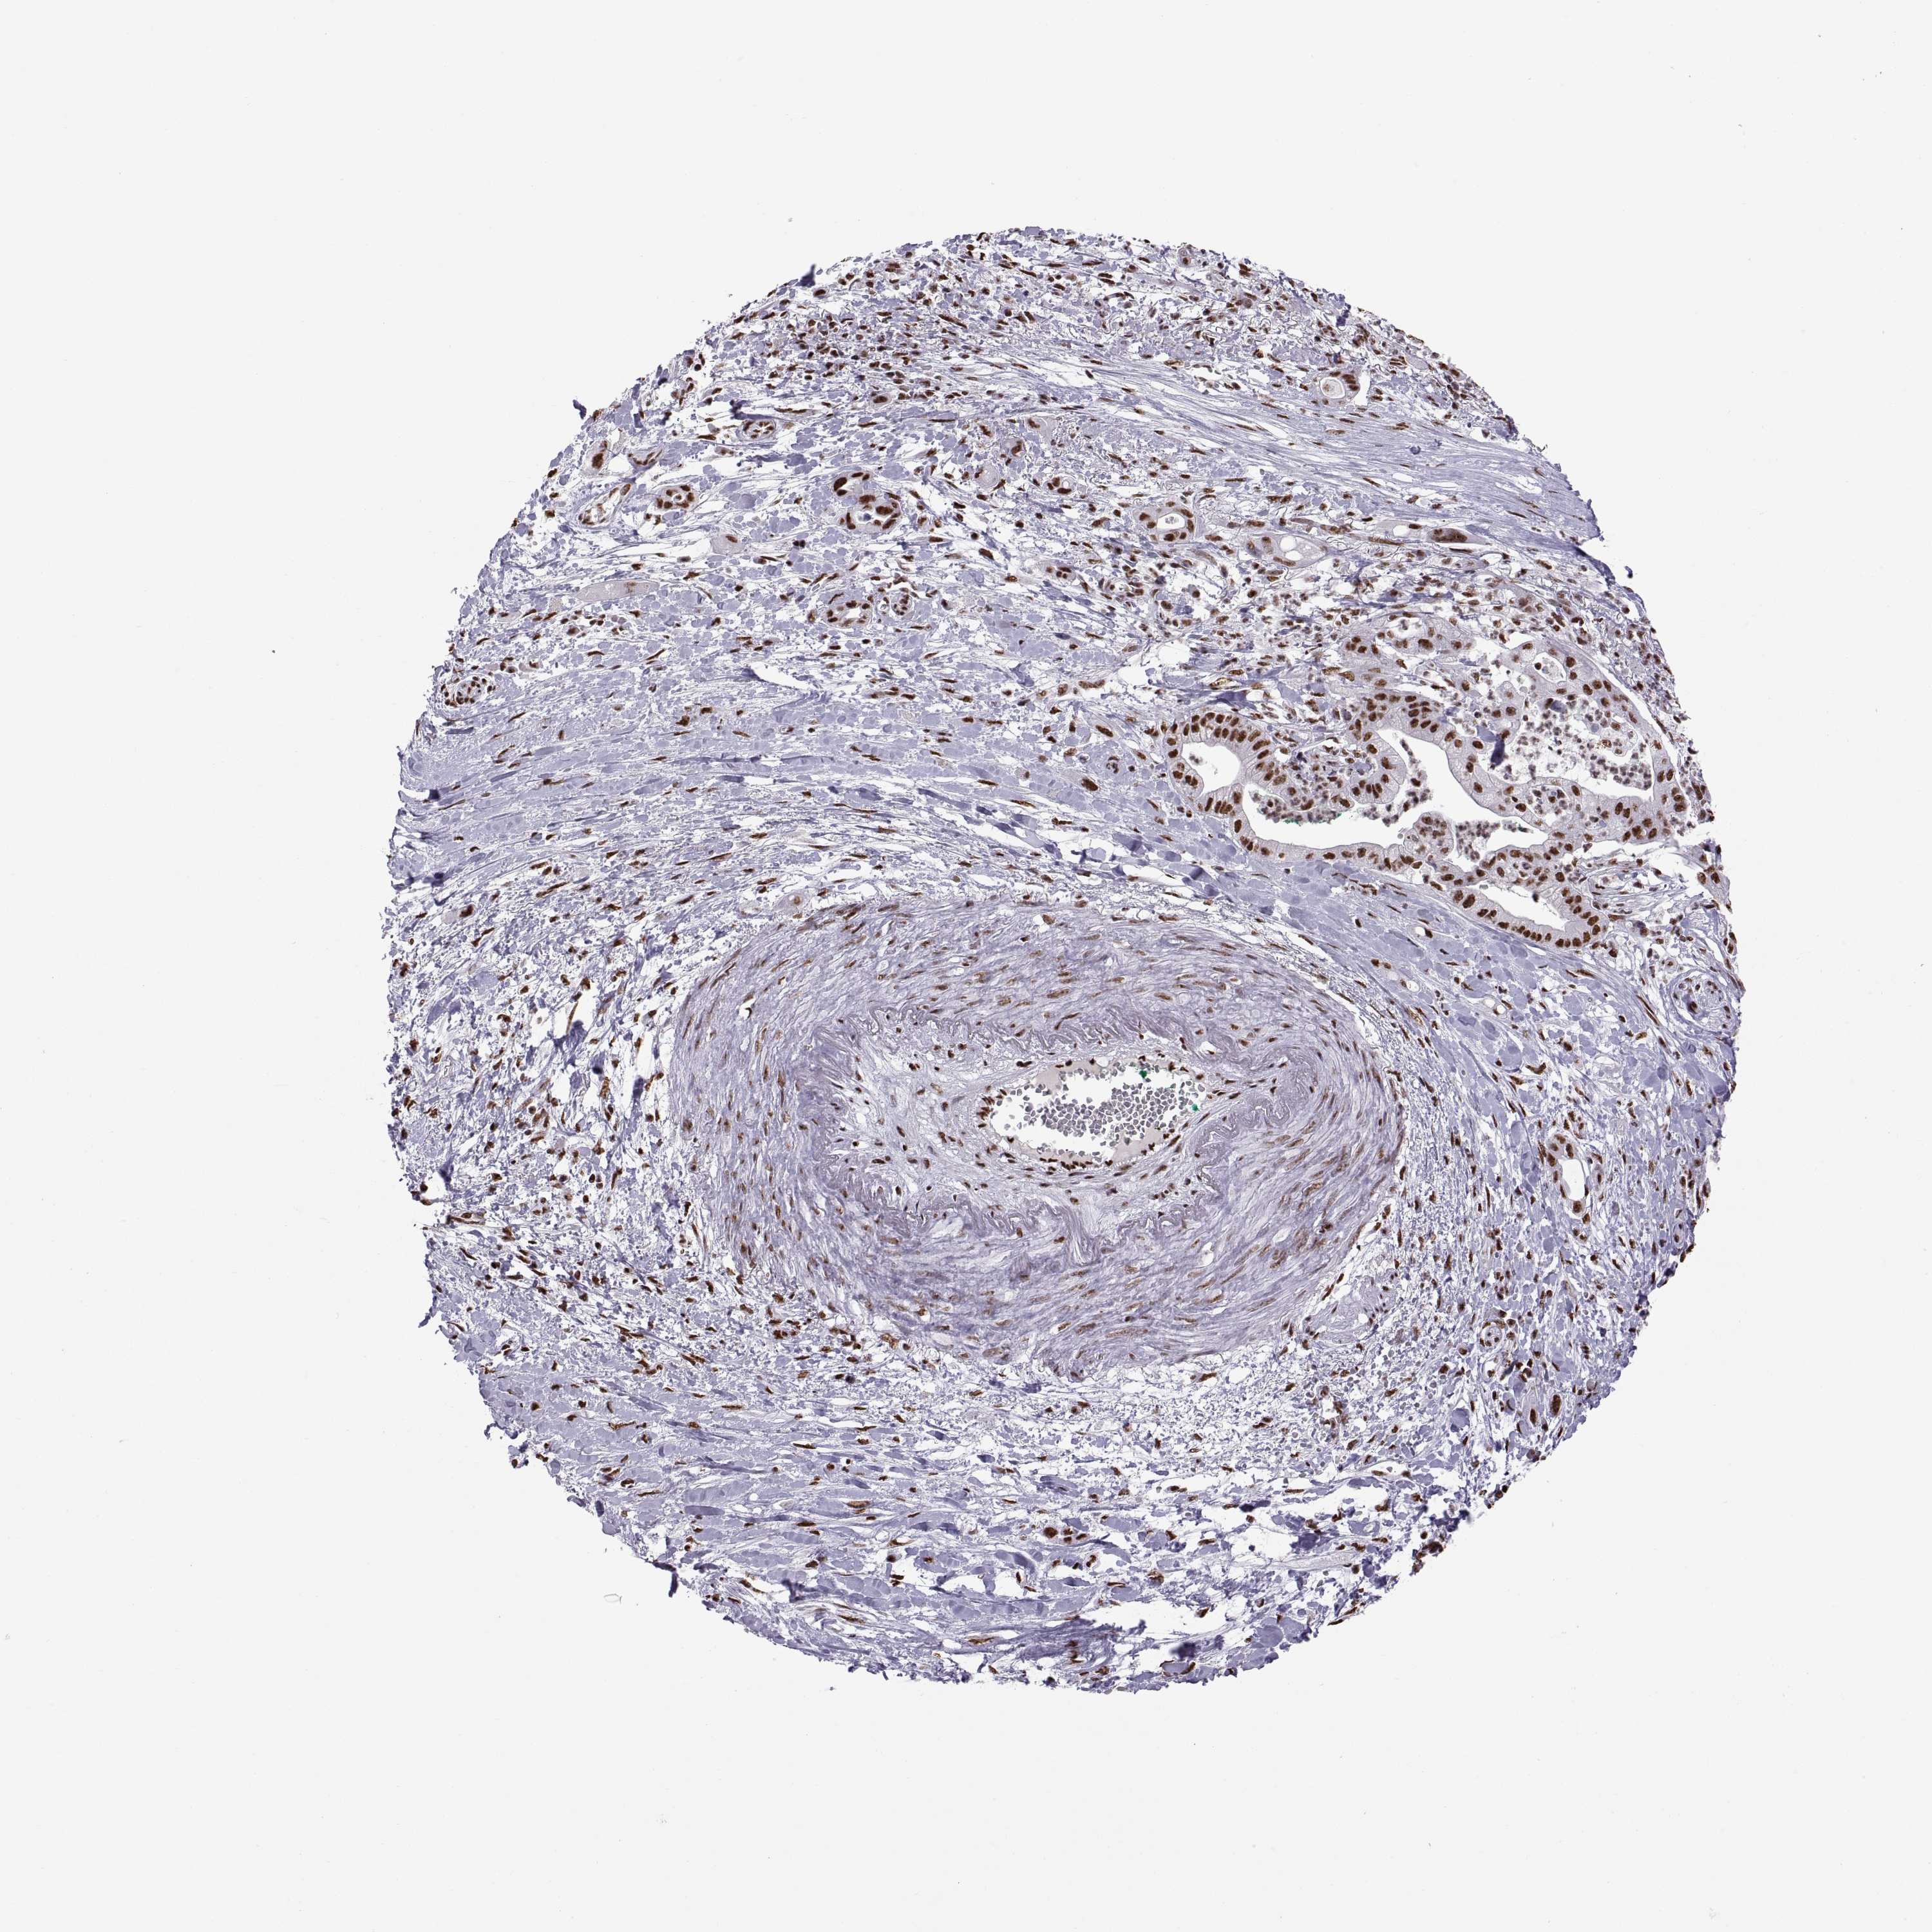

PANCREATIC CANCER - Protein expressioni

A mouse-over function shows sample information and annotation data. Click on an image to view it in a full screen mode. Samples can be filtered based on level of antibody staining by selecting one or several of the following categories: high, medium, low and not detected. The assay and annotation is described here.

Note that samples used for immunohistochemistry by the Human Protein Atlas do not correspond to samples in the TCGA dataset.

Antibody stainingi

Antibody staining in the annotated cell types in the current human tissue is reported as not detected, low, medium, or high, based on conventional immunohistochemistry profiling in selected tissues. This score is based on the combination of the staining intensity and fraction of stained cells.

Each image is clickable and will lead to virtual microscopy that enables deeper exploration of all samples and also displays staining intensity scores, fraction scores and subcellular localization as well as patient and tissue information for each sample.

Antibody HPA069985

Antibody CAB005883

Antibody CAB078687

Antibody CAB080398

Adenocarcinoma, NOS

Adenocarcinoma, metastatic, NOS